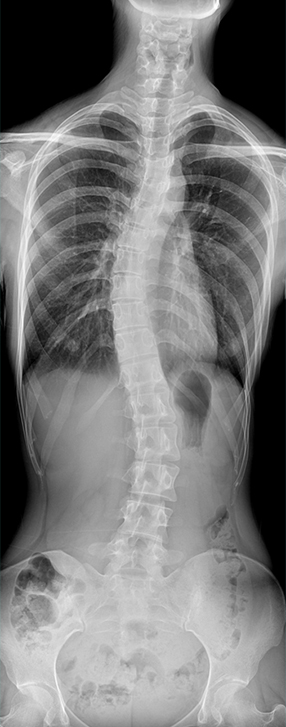

临床图像